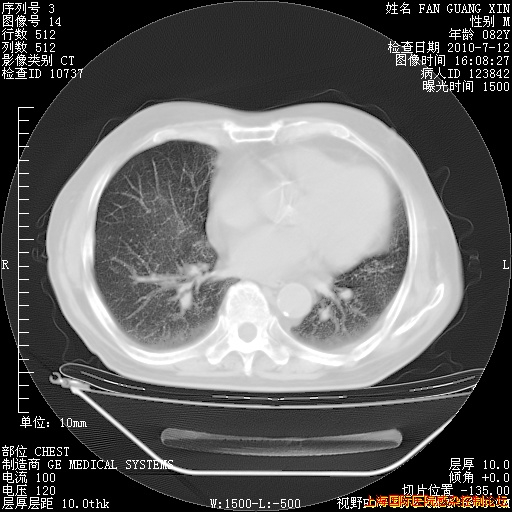

补发6月12日肺部CT肺窗

6月12日肺窗

6月10日改甲强龙80mg qd ,在南京年会期间体温不稳,18日有一次寒战后体温达39度。19日开始用甲强龙60mg bid ,加量后第二天就不发热。本打算在两周后即7月3日减量,但是7月2日洗澡受凉、发热、咳嗽、鼻音,口服复方大青叶片,甲强龙120mg用到9日(整整20天)。

整整相隔30天的肺部CT好像有所好转啊。甲强龙减量第3天,需要观察体温。

海管,自昨日你和我通完话后,不知您岳父消化道症状有无缓解?体温怎样?阅读7.12日胸部ct,个人认为目前激素治疗是有效的,甲强龙减量是适宜的。因在抗痨治疗,需密切观察肝功、肾功能和血常规。不过,老年、长期住院和大量使用激素,很担心菌群失调发生